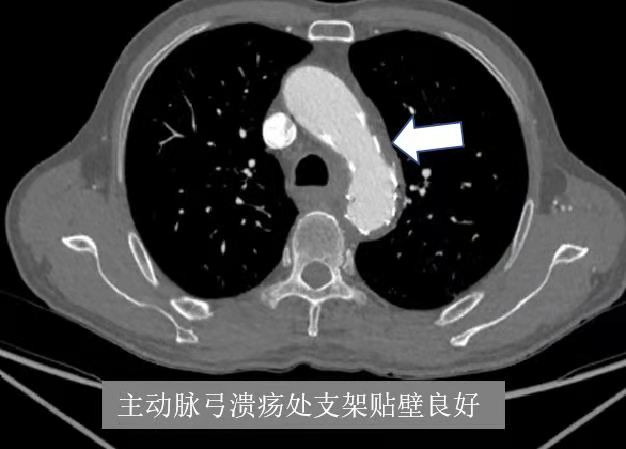

为此,张大爷找到独墅湖医院介入与血管外科张喜成主任,医生们根据影像,认为主动脉弓部穿透性溃疡最危险,很容易导致夹层或破裂引起生命危险,另外左锁骨下动脉、髂动脉均完全闭塞,这些都给治疗上带来挑战。经研究讨论后医生们决定同期解决多处血管问题。手术在我院先进的复合手术室进行,张主任、黄献琛博士和顾铖涛医师密切配合,术中因锁骨下动脉闭塞段的钙化很严重,很难开通,但他们艺高胆大,采用双向穿刺技术成功开通血管,然后用覆膜支架覆盖主动脉的溃疡,但由于溃疡距离左锁骨下动脉较近,故他们采用“浮潜”技术,既盖住了溃疡又保证分支血管的畅通。最后他们又成功开通了闭塞的左髂动脉,并植入血管支架解除了狭窄。

术后第二天张大爷就能下床活动,术后5天患者复查CT提示支架通畅,在位良好,支架贴壁紧合。